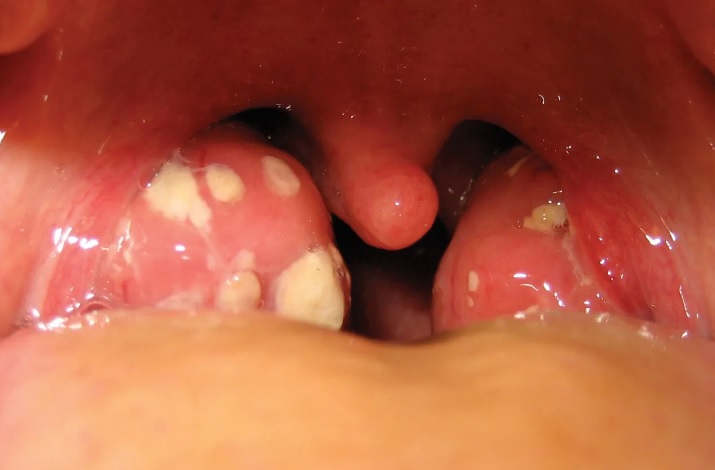

The tonsils are two soft masses of lymphoid tissue (lymph nodes) located on either side at the rear of the throat. Tonsils help the body fight infections by forming antibodies that work to nullify disease-causing microbes such as viruses and bacteria. Medical research has proved, that the removal of tonsils (even adenoids, which are also lymphoid tissue like tonsils but located behind the nasal cavity) in children has no adverse effect on their immunity to diseases and infections.

Tonsillitis is nothing but an infection in tonsils. It is a very common condition. If you are looking for tonsillitis treatment in hyderabad, Consult our leading ENT experts at Dr. Satish Bhong

Symptoms

Sore throat

Fever

Pain in swallowing

Bad Breath

Painful and swollen lymph nodes in front of the neck

Ear pain when making a swallowing motion